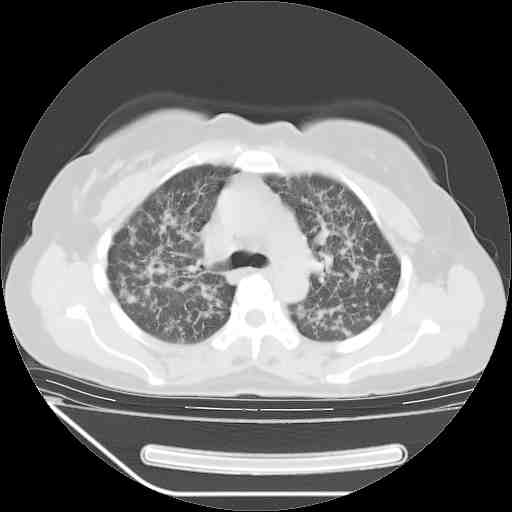

下面是今天刚刚做的,在上海治疗,吃了家属也说不清的一种药,一个月1万左右,

考虑  腺癌肺内转移,治疗较前病灶缩小、减少

支持肺癌并肺内淋巴管转移,

支持肺癌并肺内淋巴管炎,  原发灶小了,但转移较前片明显了.

支气管血管束粗而乱,考虑肺癌肺内淋巴管转移,右侧乳房第一二层软组织成份较左侧多,不会有问题吧?

支持右肺下叶周围型肺癌并肺内淋巴管炎,  原发灶小了,但转移较前片明显了.。

标准的细支气管肺泡癌呀!治疗后病情有所控制,也没治愈的迹象!